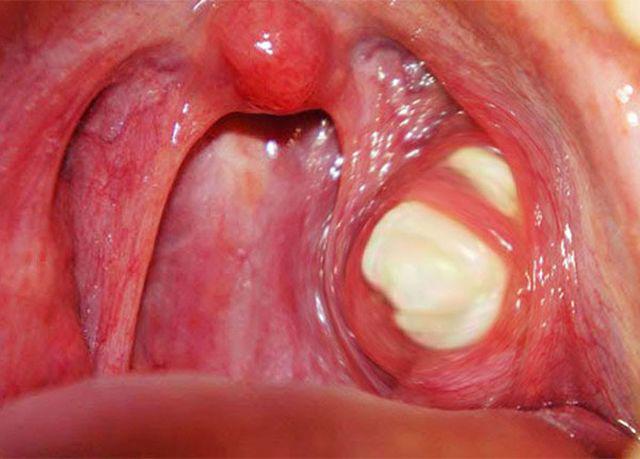

เมื่อแพทย์ตรวจด้วยการส่องกล้อง พบ “ก้อนสีขาวขุ่น” ขนาดใหญ่ติดอยู่ที่ทอนซิลด้านซ้าย ตอนแรกหญิงสาวคิดว่าเป็นเศษชีสที่กินตอนเช้า แต่แพทย์ยืนยันว่า นั่นคือ “นิ่วทอนซิล” ที่สะสมมานาน

นิ่วทอนซิล (Tonsil stone) หรือ “ก้อนบะจ่างทอนซิล” เกิดจาก:

สิ่งเหล่านี้สะสมอยู่ในร่องของทอนซิล จนกลายเป็นก้อนแข็งสีขาวขุ่น